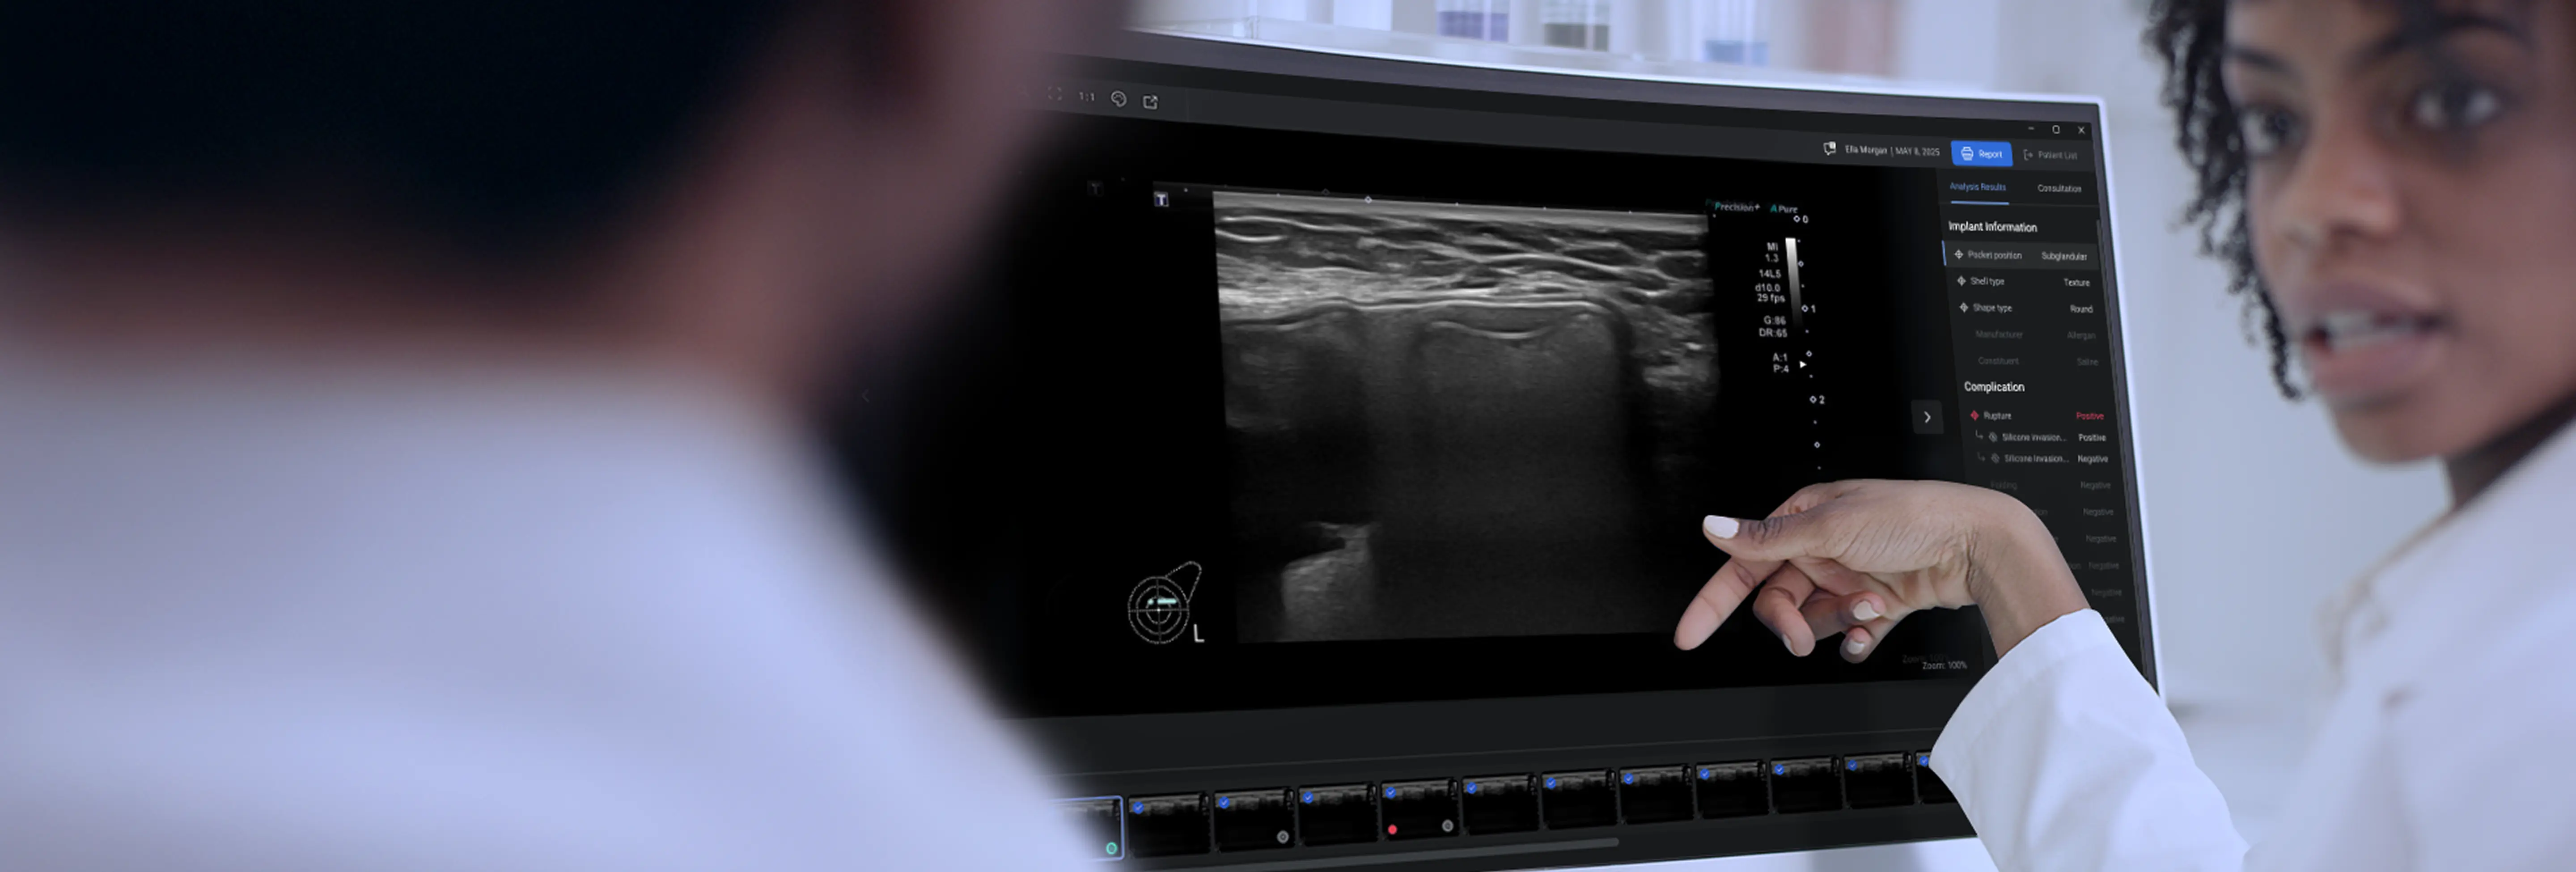

AI-Powered Breast Implant Diagnostic Tool

is the world 1st breast

implant diagnosing AI program.

Our solution helps radiologists, breast surgeons, plastic surgeons with MMG and US images for identifying the various breast implant types (texture or smooth) and complications such as rupture, thickened capsule related with capsular contracture.

W Expert serves as a valuable diagnostic tool by compensating for radiologists' limited experience in breast implant diagnosis and understanding of cosmetic surgery complications. Plastic surgeons may lack ultrasound experience, but W Expert provides essential information for planning revision surgeries. This expands the ultrasound market, enabling patients to receive more accurate diagnoses and reliable treatments.